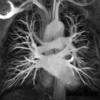

vessesls MR

Date: 01/12/2015

Views: 3230